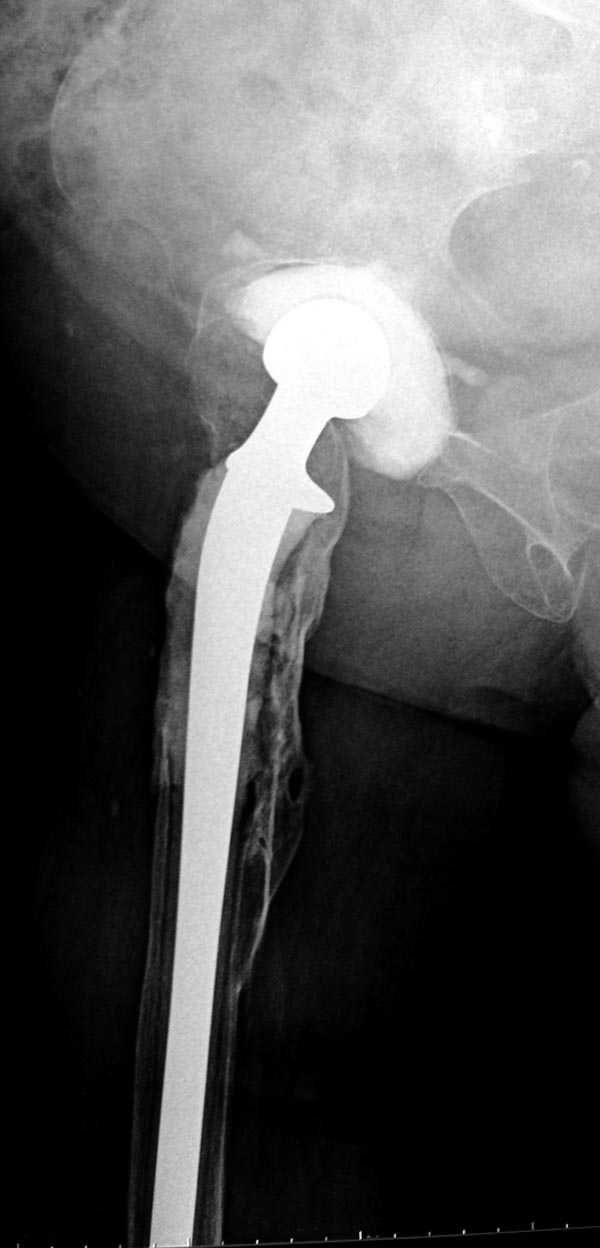

Из предложенных вариантов быстрейший результат можно ожидать после поэтапного эндопротезирования.

"Антибиотико-цементные" спейсеры после купирования

инфекции уже после первого этапа позволяют больным

передвигаться самостоятельно, иногда нагружая конечность годами.

Как-то показывал случай после осложненного тотального эндопротеза, сперва из-за отсутствия экономических возможности, а затем привыкшая к своей участи вот уже более 8 лет ходит на временном "протезе-спейсере".

Полость вертлужной впадины и проксимальное бедро были заполнены custom made временным протезом из цемента.

Для бедренного компонента можно применить старую

длинную ножку протеза и желательно малого диаметра.

Цементная смесь наносится вручную на металл и

затем доводится до ровного диаметра поверхности

снятием лишнего цемента шаблоном. Такие шаблоны были в старом интрамедуллярном наборе, различные по диаметру отверстия на металлической пластине. Протез с цементом проводится через отверстие в шаблоне для точного совпадения с размером проксимального римера. Таким образом приготовленный феморальный компонент будет

держаться в бедренной кости плотно.